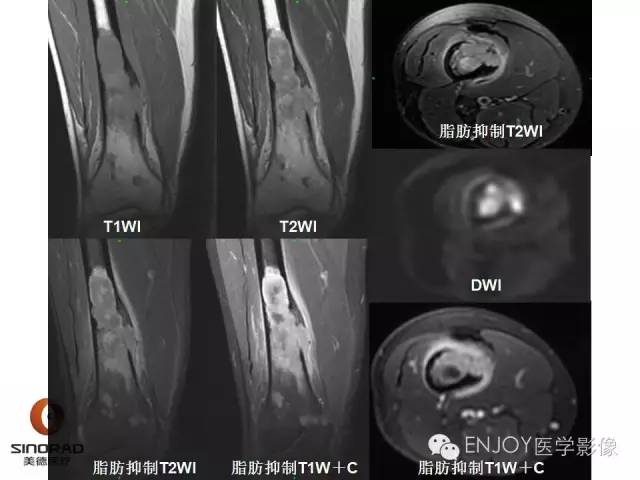

【病例】右侧股骨多形性肉瘤1例X线及MR影像表现

多形性肉瘤(以往称为:恶性纤维组织细胞瘤)